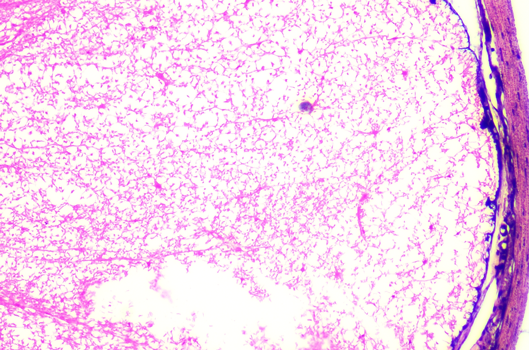

脊髓液细胞

![]() | ![]() | |

普通彩色相机采图结果 | 大恒图像相机色彩优化后 |